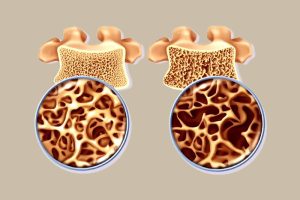

استخوانها بیش از آنچه تصور میکنیم قابلیت بازسازی دارند. پژوهشهای اخیر نشان میدهند که ورزش نه تنها تراکم استخوان را حفظ میکند، بلکه با فعالسازی مسیرهای سلولی خاص، سلولهای استخوانساز را تحریک کرده و استخوانهای تحلیلرفته را دوباره قوی میسازد. این کشف تازه نویدبخش راهی جدید برای درمان پوکی استخوان (Osteoporosis) است، بیماریای که میلیونها نفر در جهان را تحت تأثیر قرار داده و برای سالها بازسازی کامل استخوانها را دشوار کرده بود.

پوکی استخوان با کاهش تراکم و استحکام استخوانها خود را نشان میدهد و اغلب افراد مسن و زنان پس از یائسگی را تحت تأثیر قرار میدهد. کاهش قدرت استخوانها میتواند به شکستگیهای دردناک در لگن، ستون فقرات و مچ دست منجر شود و کیفیت زندگی را بهشدت کاهش دهد. درمانهای فعلی عمدتاً روند تخریب استخوان را کند میکنند، اما توان بازسازی کامل بافت استخوان محدود است.

تحقیقات جدید که بر اساس گزارش خبرواژه منتشر شده است، مسیر مولکولی تازهای را شناسایی کرده که قادر است سلولهای استخوانساز (Osteoblasts) را فعال کند. فعالسازی این مسیر باعث افزایش تولید بافت استخوانی و تقویت ساختار آن میشود. آزمایشهای اولیه روی مدلهای حیوانی نشان میدهند که این مسیر میتواند روند پوکی استخوان را معکوس کند و امید تازهای برای بیماران فراهم آورد.

فعالیتهای تحمل وزن و تمرینات مقاومتی، مسیر مولکولی بازسازی استخوان را بهطور طبیعی تحریک میکنند. فشار مکانیکی وارد بر استخوانها طی ورزش، سلولهای استخوانساز را فعال کرده و فرآیند تولید بافت جدید را آغاز میکند. به این ترتیب، ورزش علاوه بر حفظ تراکم استخوان، روند بازسازی بافتهای تحلیلرفته را نیز تسریع میکند.

یکی از نتایج کلیدی تحقیقات جدید، اثربخشی ترکیبی ورزش و داروهای فعالکننده مسیرهای مولکولی است. ترکیب این دو روش، باعث افزایش فعالیت سلولهای استخوانساز و بازسازی بهتر استخوان میشود. این رویکرد میتواند چارچوبی نو برای درمان پوکی استخوان فراهم آورد و عوارض جانبی درمانهای رایج را کاهش دهد.

کشف مسیر مولکولی بازسازی استخوان، راه را برای توسعه داروهای هدفمند هموار میکند. داروهایی که قادر باشند سلولهای استخوانساز را مستقیم فعال کنند، میتوانند تراکم از دست رفته استخوان را بازگردانده و کیفیت زندگی بیماران را بهبود بخشند. در کنار درمانهای دارویی، ورزش منظم بهعنوان بخش جداییناپذیر پیشگیری و درمان اهمیت ویژهای دارد. ترکیب ورزش و داروهای نوین امید تازهای برای بازسازی استخوانها و مقابله با پوکی استخوان ایجاد کرده است.

استخوانها دیگر ساختارهای غیرقابل بازسازی نیستند. با فعالسازی مسیرهای سلولی مناسب و ورزش منظم، میتوان روند بازسازی استخوانها را سرعت بخشید. این کشف، افق تازهای برای درمان پوکی استخوان باز کرده و نشان میدهد که حتی استخوانهای تحلیلرفته نیز قابلیت بازگشت و قوی شدن دارند. با رعایت ورزش روزانه، تغذیه مناسب و استفاده از درمانهای نوین، میتوان سلامت استخوانها را بهبود بخشید و زندگی فعالتری داشت.